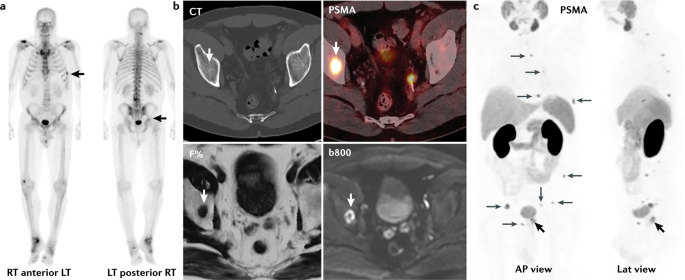

Review of bony windows on CT imaging allows identification of sclerotic metastases and ensures accurate staging of metastatic bone disease Fig. Tietze syndrome is similar to costochondritis but less common. Nasopharyngeal carcinomas appear as soft tissue masses most commonly centered at the fossa of Rosenmüller.

Cancer invades bone directly osteolytic metastases. CT is not only more readily available but is also the ideal modality to assess early bony involvement. Bladder cancer is the ninth most common cancer in the UK accounting for 27 of all the new cancers cases.

In 2018 there. However it commonly fails to diagnose osteoblastic or sclerotic metastases.